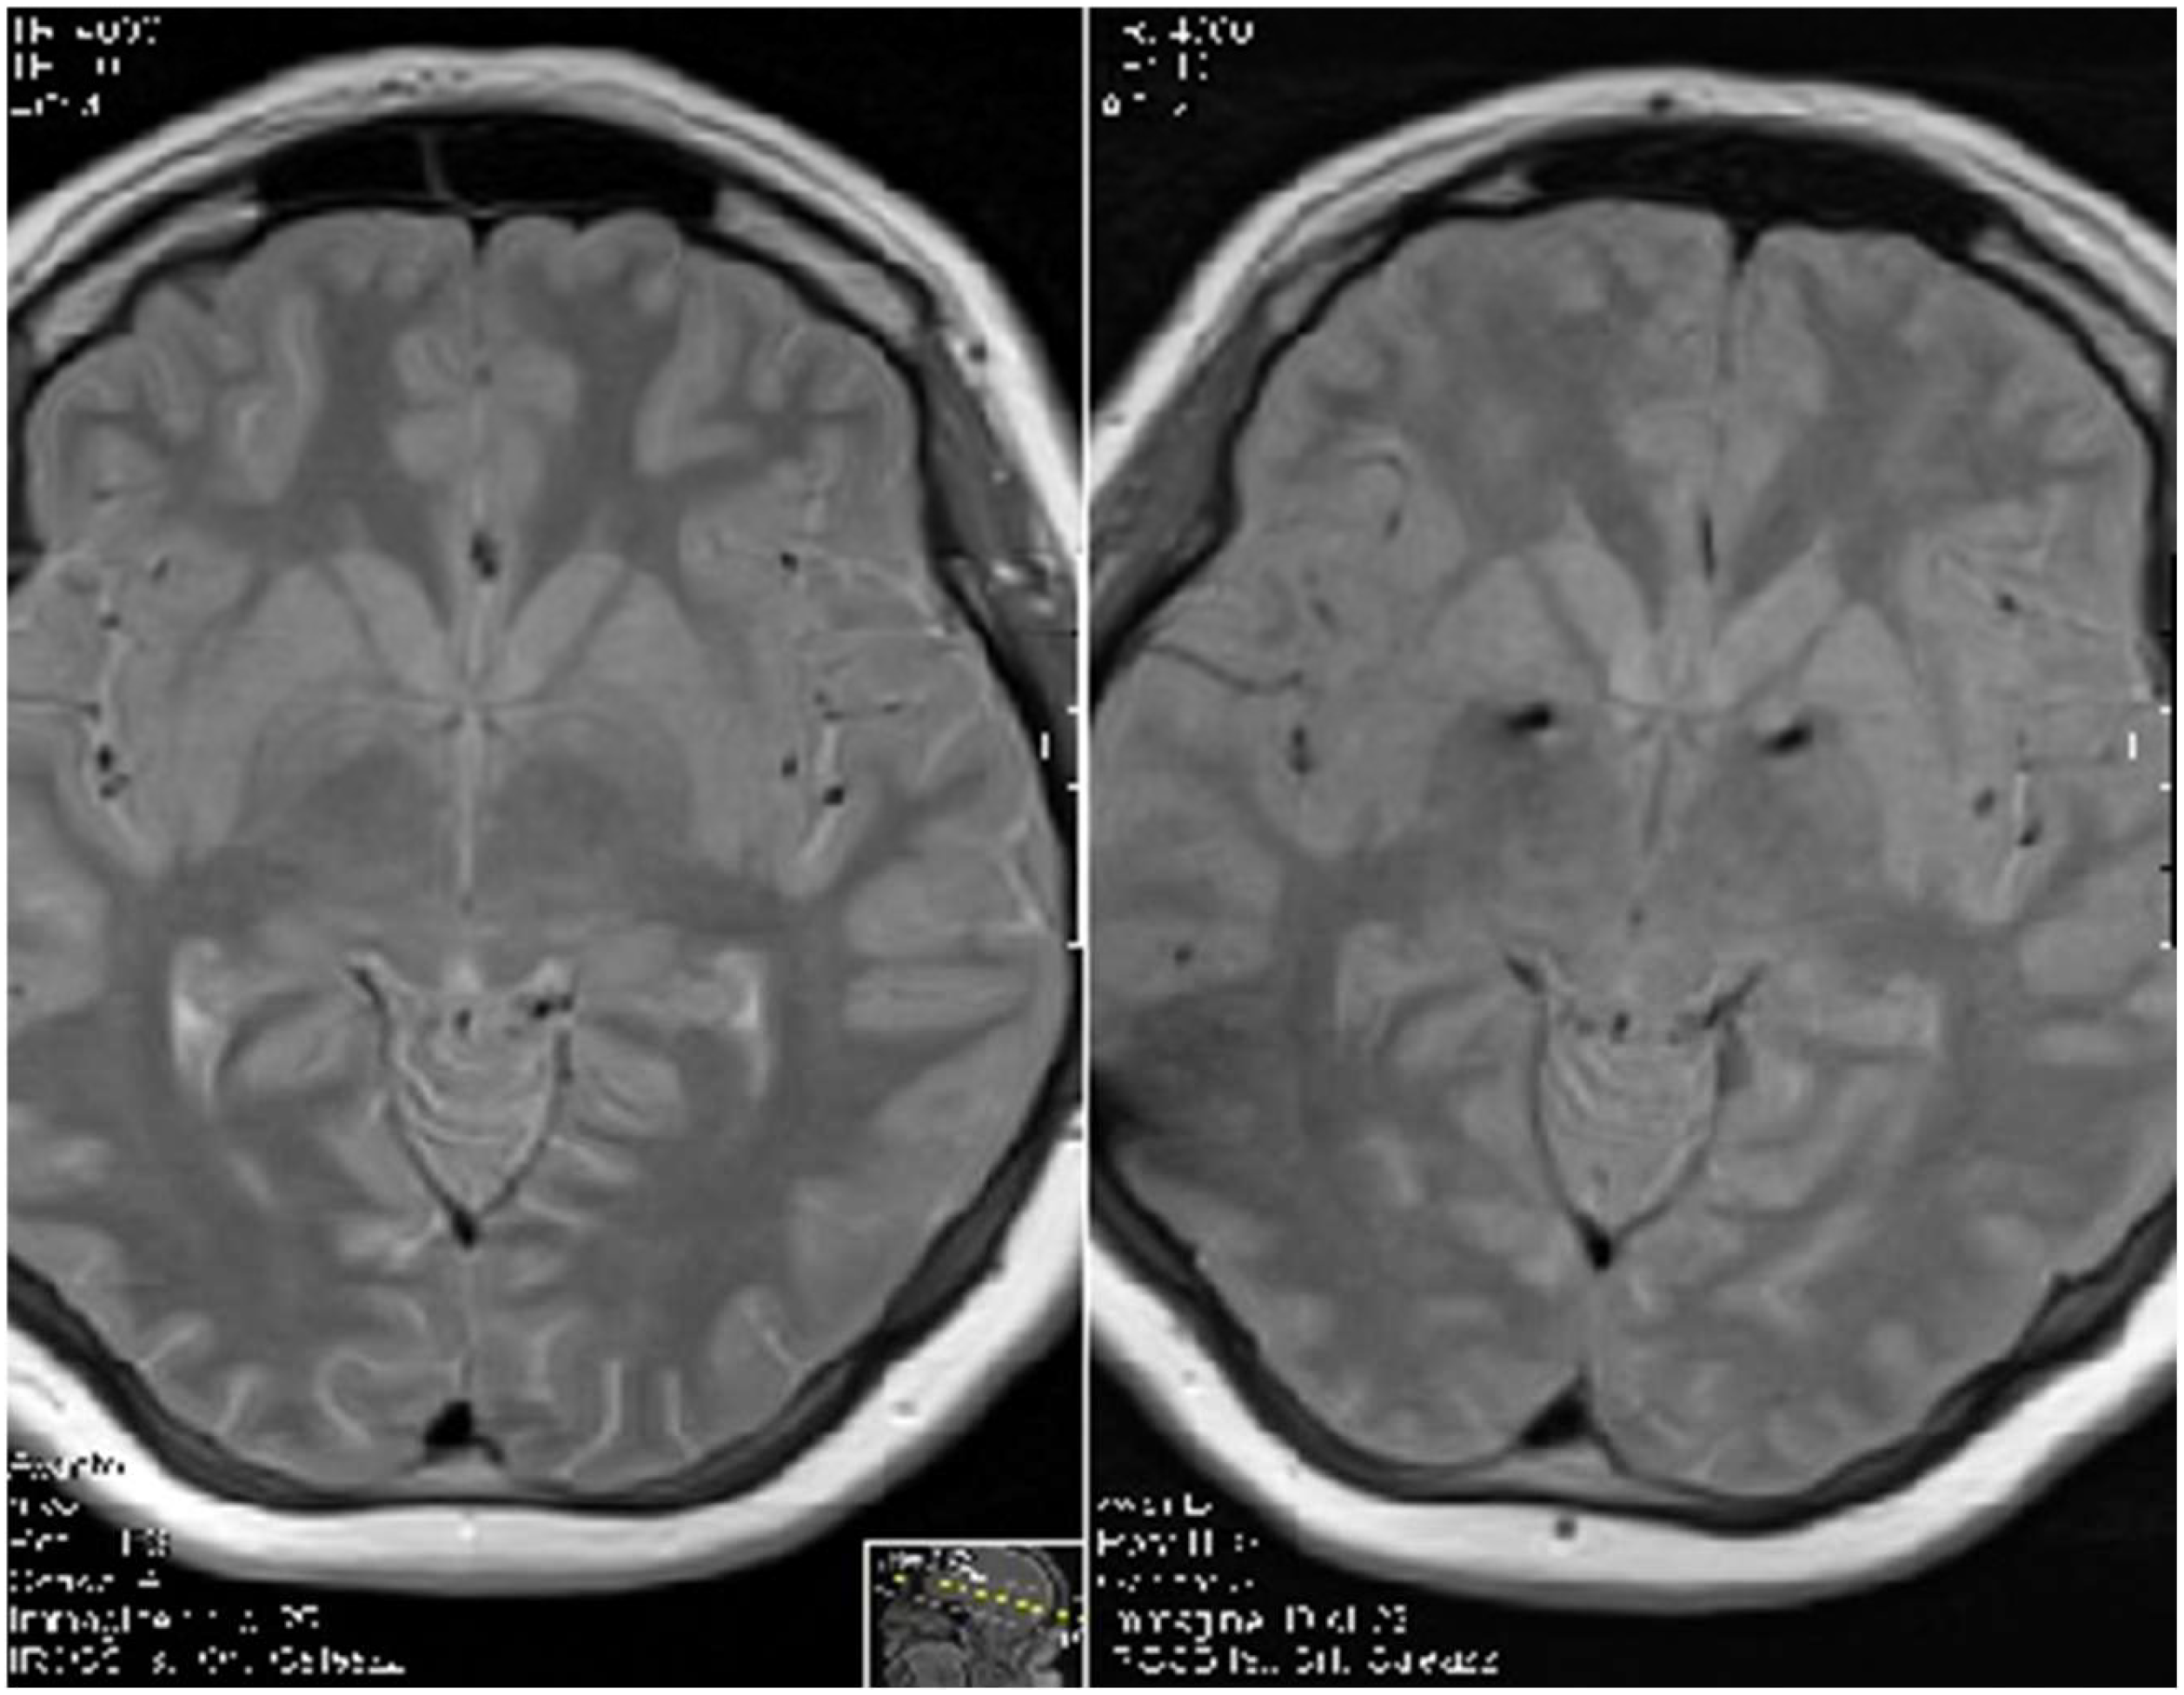

- Servello, D.; Zekaj, E.; Saleh, C.; Dina, C.Z.; Porta, M. Sixteen Years of Deep Brain Stimulation in Tourette’s Syndrome: A Critical Review. J. Neurosurg. Sci. 2016, 60, 218–229. [Google Scholar]

- Servello, D.; Zekaj, E.; Saleh, C.; Lange, N.; Porta, M. Deep Brain Stimulation in Gilles de la Tourette Syndrome: What Does the Future Hold? A Cohort of 48 Patients. Neurosurgery 2016, 78, 91–100. [Google Scholar] [CrossRef]